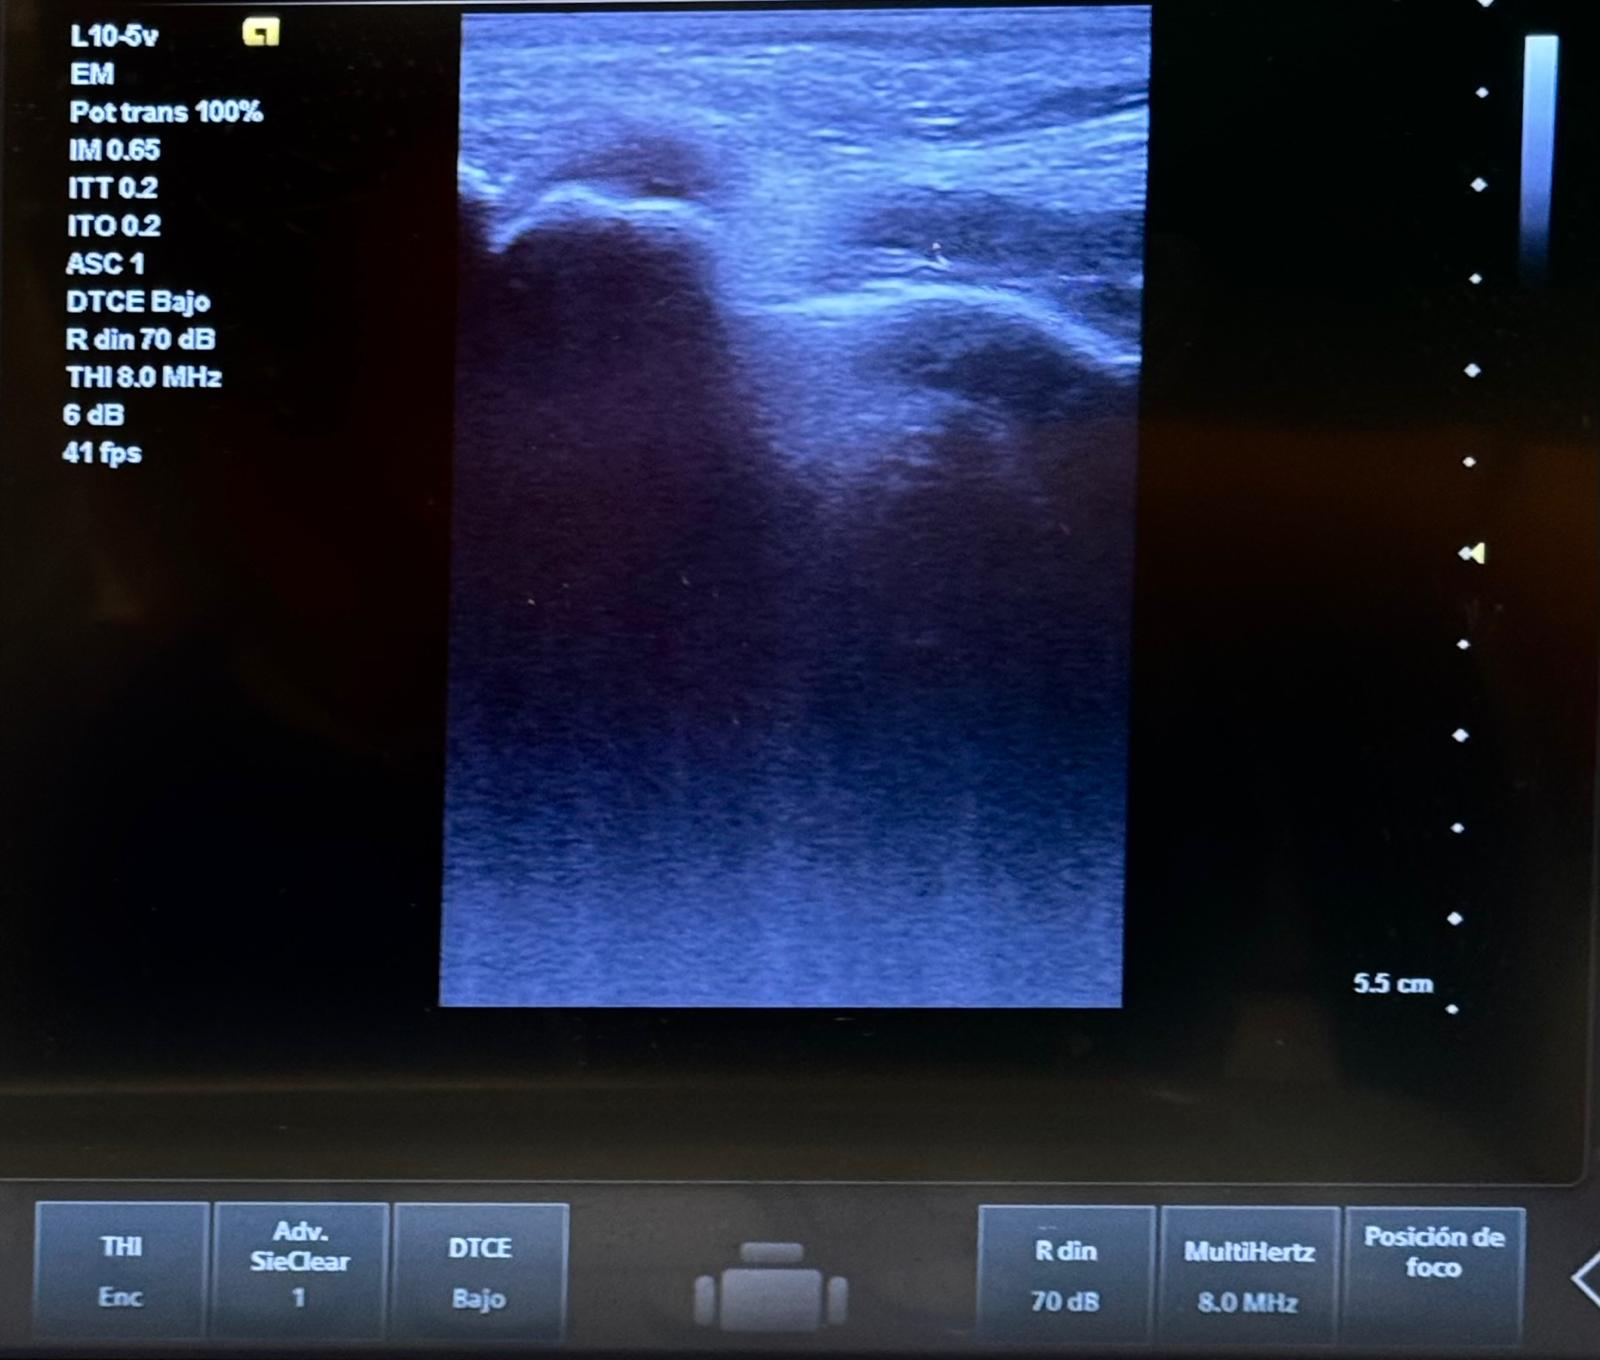

Pruebas complementarias:

La artritis séptica requiere diagnóstico rápido para prevenir daños articulares permanentes. En medicina de familia, la identificación precoz de signos como dolor, tumefacción y calor local es clave para derivar adecuadamente. La analítica, la ecografía y la artrocentesis son esenciales para confirmar el diagnóstico y guiar el manejo inicial en urgencias.